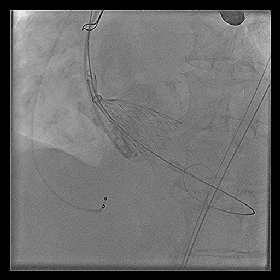

◆2015年1月17日行TAVI术。

◆植入29mm CoreValve人工支架瓣膜一枚。

术后症状明显缓解,近一年未因心衰住院;

一年期复查心超,未见主动脉瓣狭窄和关闭不全。